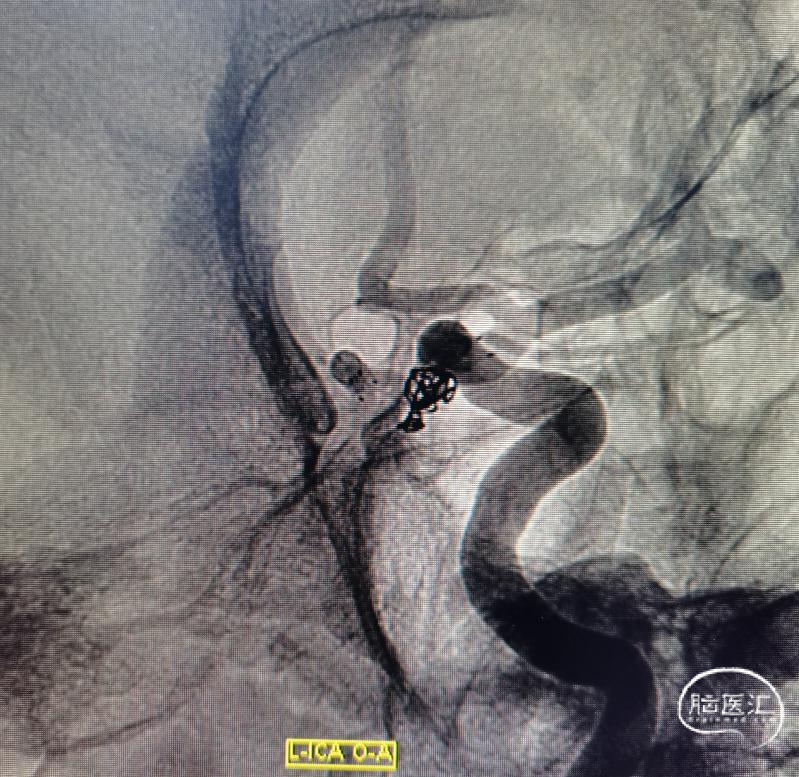

圈已到位,准备压个支架。在后交通动脉起始处再放个圈,加强防护,防止复发。

直接放上支架,虽然支架留到颈内动脉,但是如果摆尾不好,后果还是比较惨的,因此选择了一条比较安全的方案。手术顺利。